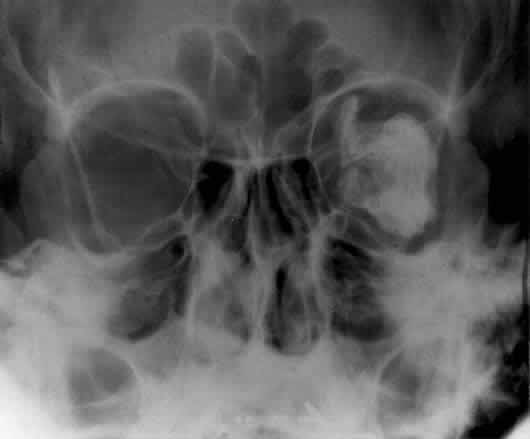

The optic foramen should measure 6 mm vertically and 5 mm horizontally. Asymmetry greater than 1 mm or a vertical dimension greater than 6.5 mm is considered abnormal.15,27 Ninety-eight percent of patients have optic canals that vary by less than 1 mm.27 Concentric enlargement of the foramen and optic canal can be seen with optic nerve gliomas, meningiomas, neurofibromatosis, and less commonly an aneurysm of the ophthalmic artery (Fig. 16). A decrease in the optic foramen and canal dimension can be seen in fibrous dysplasia, Paget's disease, hyperostosis secondary to a meningioma, or microphthalmos (Fig. 17, Table 1).

Fig. 16. Oblique apical projections showing the optic foramen. The left optic foramen has concentric enlargement from an optic nerve glioma. The foramen should not have greater than 1 mm of asymmetry.

Fig. 17. Bilateral optic canal compression from fibrous dysplasia. There is diffuse bone thickening in each orbit. Note small size of optic foramen (arrow).